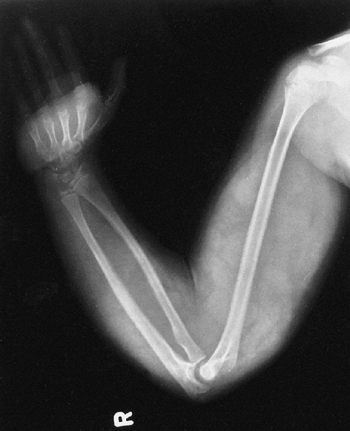

affect the ulna, radius, femur, or clavicle (115,116,117,118,119,120,121).

In each of these locations, there is a course similar to that in the

tibia, with bone loss and difficulty in achieving union (Fig. 9.13). Not all pseudarthroses of the forearm require treatment (122), but if they are symptomatic, the available options include proximal and distal synostosis to produce a single-bone

forearm, the use of a vascularized fibula graft, or resection of the

pseudarthrosis with shortening of the forearm and internal fixation (123).

Figure 9.13

Neurofibromatosis in a 3-year-old patient. The radiograph shows progressive pseudarthrosis of the radius and ulna after a pathologic fracture. A: Fracture through the cystic lesion of the radius and thinning of the mid-ulna. B: After 10 months of cast immobilization, pseudarthrosis affects the radius and ulna. (From Goldberg MJ. The dysmorphic child: an orthopedic perspective. New York: Raven Press, 1987, with permission.) |